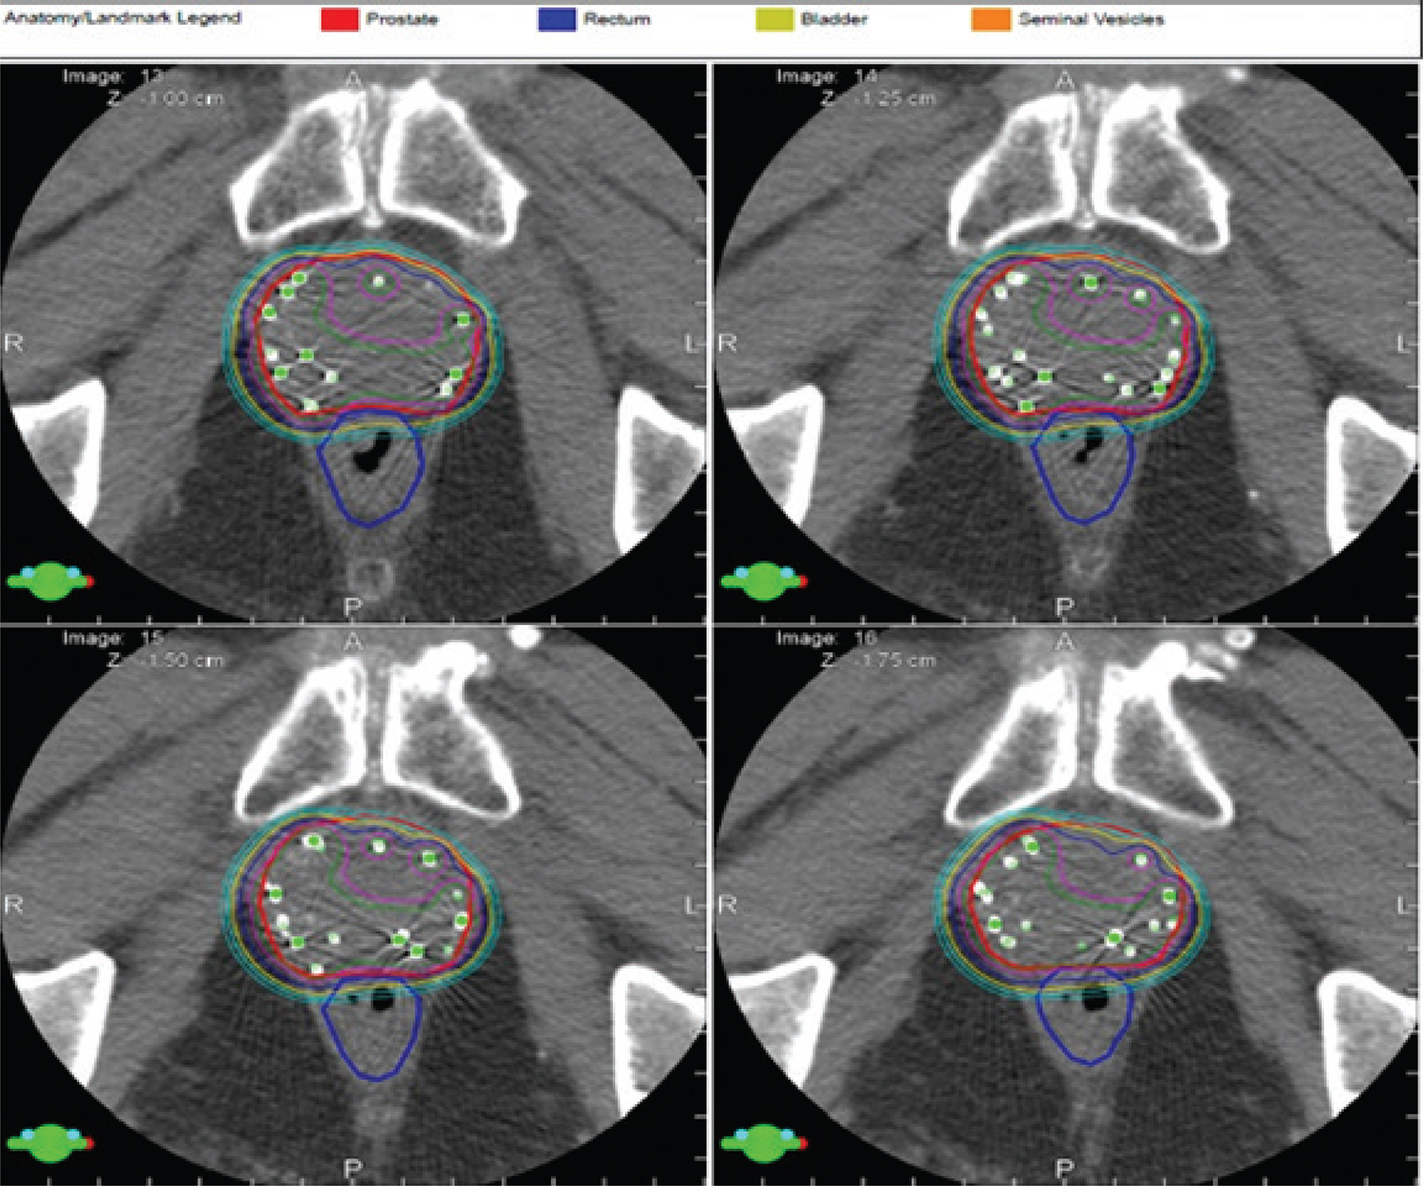

Process improvements in radiation oncology have demonstrated outstanding progress in the care of prostate cancer patients. Volumetric planning has provided security in radiation therapy target definition and modern imaging tools including multi-parametric magnetic resonance imaging. New metabolic agents used for positron emission tomography have provided more confidence that tumor targets are well defined and treated with accuracy (24). Intensity modulation has permitted radiation oncologists to place sharper dose gradients across normal tissue structures, including bladder and rectum, with increased dose to tumor target, permitting higher dose to tumor targets with no additional clinical morbidity. This has served to expand our role in prostate cancer to treat early metastatic disease with success (3, 5, 6). Decreased dose and sharper dose gradients to normal tissue, aided by intensity modulation, decrease radiotoxicity to the rectum, small bowel, bone structures including the acetabulum, and bladder (Figure 1).

Fig 1

Figure 1. Process improvements in radiotherapy of prostate cancer. A, Dose gradients across bladder and rectum for a traditional radiation therapy using intensity modulation. Daily image guidance allows for adjustments in positioning each day relative to target motion. B, A cone beam computer tomography image obtained pre-therapy to validate target positioning on a daily basis. The security provided by image guidance permits titration in planning target volumes which in turn decrease dose to normal tissue further. The use of volume modulated arcs permits rapid therapy delivery over a few minutes giving confidence to both physicians and patients in limiting intrafraction motion of targets further promoting security in daily treatment execution. C, Arc geometries applied to prostate cancer care. Optical tracking provides both stability and security in daily positioning and monitors external motion during therapy. D, An example of optical tracking in a prostate cancer patient. Image courtesy of the Department of Radiation Oncology, UMass Chan Medical School and UMass Memorial Health.